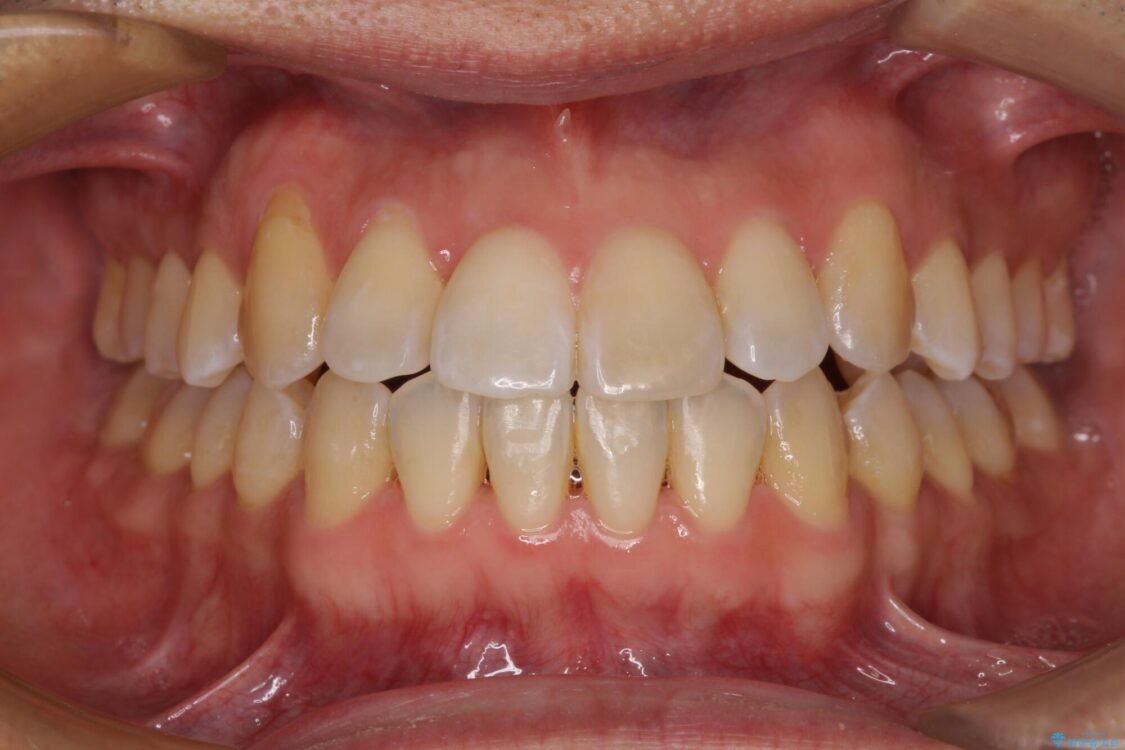

治療後

• 左右の八重歯が気になる ワイヤー装置での咬み合わせ改善 治療後画像